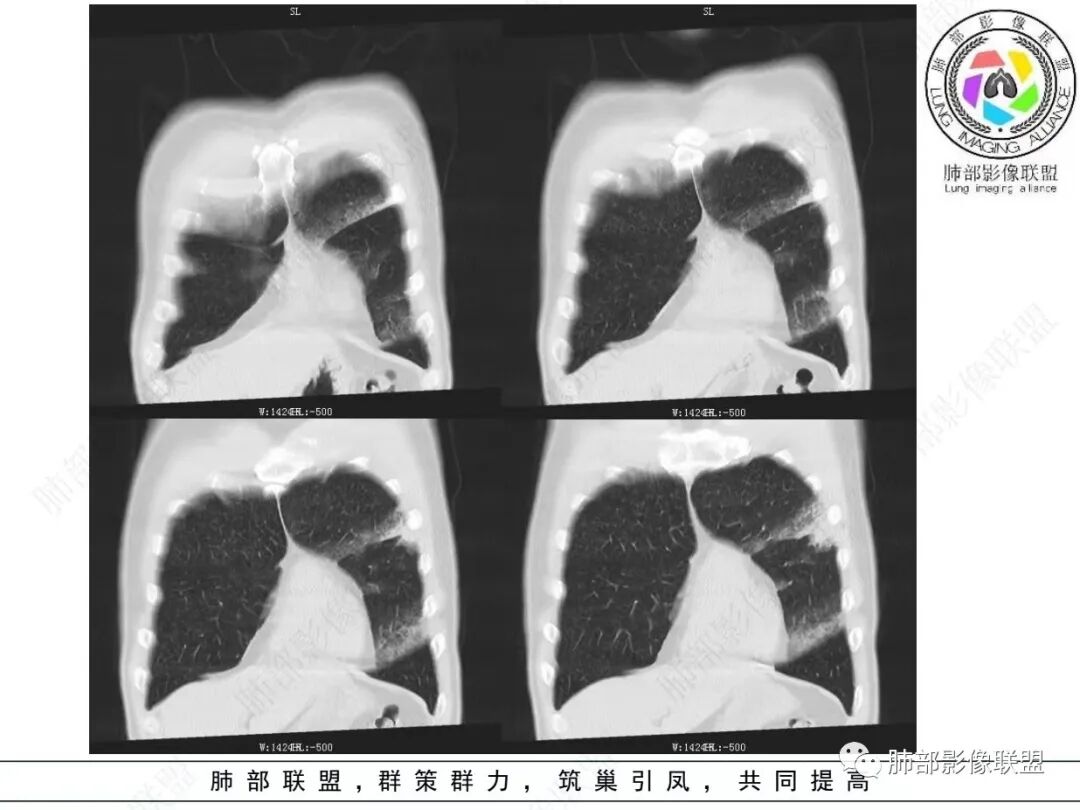

男,46,咳嗽半年,加重10天,白粘痰,偶有痰血。胸部CT:左肺上叶舌叶大片实变影,边缘GGO,长轴沿胸膜及叶裂展开,重力依赖,胸膜叶裂阻隔,内见蜂窝,钱币征,枯枝。强化不均匀,血管造影征。考虑粘液腺癌,鉴别大叶性肺炎、干酪性肺炎等。

糊墙征   蜂窝征

GGO部分边界清,近实变区密度高

2.左肺上叶大片状混合密度影,未见空洞,实变影主要位于胸膜下,长轴与胸膜平行,实变区内部密度不均、其内可见多发小斑片状低密度影,磨玻璃影多位居肺门一侧,可见网格,磨玻璃影边界多可分辨,重力分布趋势。病灶区支气管显示较为通畅,进入外围实变区渐至消隐。病灶轻度不均匀低强化,病灶区肺动脉显示较良好,未见破坏。

双肺广泛分布微小磨玻璃密度结节影,腺泡结节样分布,密度大小较为均匀一致。